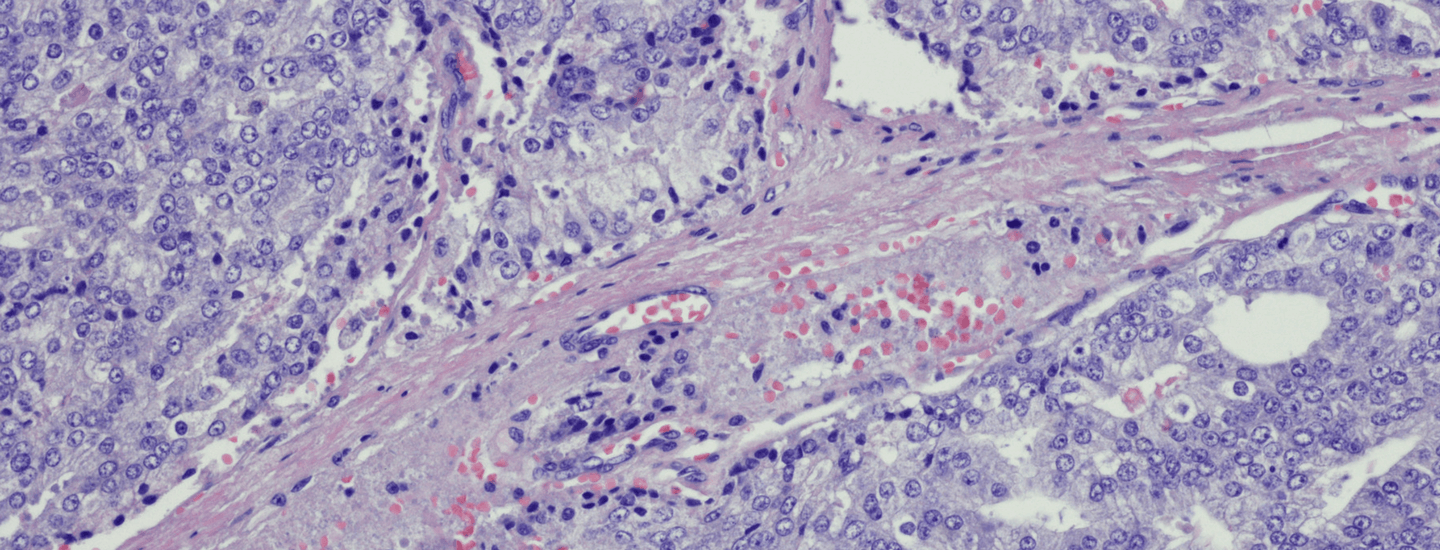

from shutterstock.com

If an abnormal PSA reading is confirmed, prostate biopsy is carried out as the definitive diagnostic test for prostate cancer. Infectious risks of prostate biopsy can be mitigated by alternative techniques such as the transperineal approach where the biopsy needle passes through skin rather than through the rectum as is usual. Many Australian centres now use transperineal biopsy.

Work from Australian researchers has also shown that magnetic resonance imaging (MRI) scans may help further refine biopsy accuracy. The use of MRI as an adjunct to prostate biopsy appears to enhance the detection of aggressive prostate cancer and reduce the detection of indolent prostate cancer.